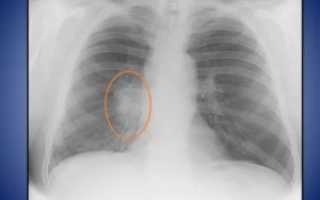

Опасной, но, к счастью, нечасто встречающейся причиной того, что корни легких уплотнены и расширены, является онкологический процесс в бронхах и органах средостения. Такой процесс, как правило, односторонний, поэтому изменение корня легкого наблюдается только с одной стороны.

После проведения обзорной рентгенографии грудной полости в двух проекциях врач-рентгенолог ставит заключение: «Корни легких уплотнены и малоструктурны».

Нарушение структуры корня легкого, то есть невозможность отличить сосуд от бронха, появление затемнения на корне, обычно встречается при первичном туберкулезе, онкологических процессах.

На рентгенограмме при обширном туберкулезе или центральном раке легкого вместо корня может визуализироваться тень различных контуров, представляющая собой очаг (до 10 мм диаметром) или инфильтрат (более 10 мм).